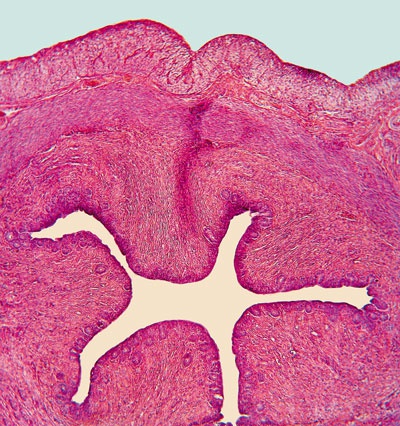

Иллюстрация к книге — О чем говорят анализы. Секреты медицинских показателей - для пациентов [i_014.jpg]

Рис. 13. Стократное увеличение поперечного среза уретры